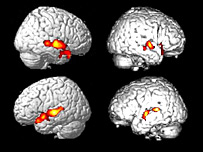

Farklı faaliyetler beynin farklı bölgelerini harekete geçiriyor

Beyin filmleri, beynin konuşmaya dair bölgelerinin sağlıklı deneklerle aynı şekilde aydınlandığını gösterdi.

Bu sırada da beynin uzuvların hareketinden sorumlu motor kontrol bölümleri aydınlandı.